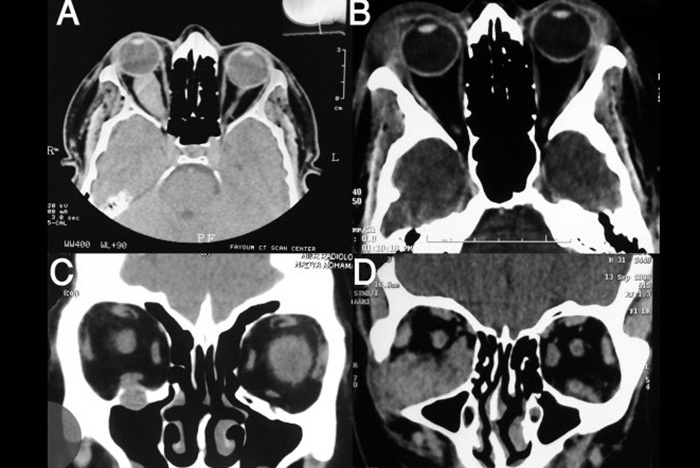

Главное предназначение исследования – определить наличие патологических состояний глазницы, а именно травмы ее стенок, переломы костей и новообразования. Помимо перечисленного сканирование хорошо зарекомендовало себя при диагностике заболеваний глазного яблока и его мышц, артерий, питающих органы зрения. Поскольку глазница состоит из мелких структур, ее осмотр должен проходить на самых современных томографических аппаратах, позволяющих применить мультиспиральное сканирование. Такая диагностика гораздо быстрее по времени и точнее, чем обычная спиральная компьютерная томография.

При обследовании глазных орбит на КТ снимки делаются прицельно. Для осмотра анатомической области используют три проекции: переднюю, боковую и горизонтальную. Благодаря этому изображения отразят множество патологий органов зрения. Среди заболеваний будут:

С помощью компьютерной томографии проще осмотреть костные структуры, вот почему ее используют, если есть предположение на переломы стенок орбиты.

Для выявления болезней глазных яблок и мышц, отвечающих за их движение, чаще назначают МРТ. Когда магнитно-резонансная диагностика обследуемому запрещена, то могут использовать КТ. При этом подбирают режимы сканирования, при которых мягкие ткани будут визуализироваться наилучшим образом.

Поскольку с годами количество злокачественных новообразований глаз стремительно растет, при таких диагнозах метод применяется для выявления масштаба разрастания злокачественных клеток, как в глазнице, так и за ее пределами. Раковые образования находят по степени контрастирования (злокачественная опухоль, накопившая контраст, становится ярче участков без патологий), смотрят насколько оттеснены расположенные рядом ткани, вовлечены ли в воспалительный процесс соседние структуры. По этим показателям определяют стадийность заболевания и назначают необходимое лечение.

Точные снимки на КТ можно создавать, применяя трехмерную реконструкцию изображения. Используя специальную программу, специалисты получают 3D-фото обследуемой области. В дальнейшем его можно рассмотреть на мониторе с любой стороны.